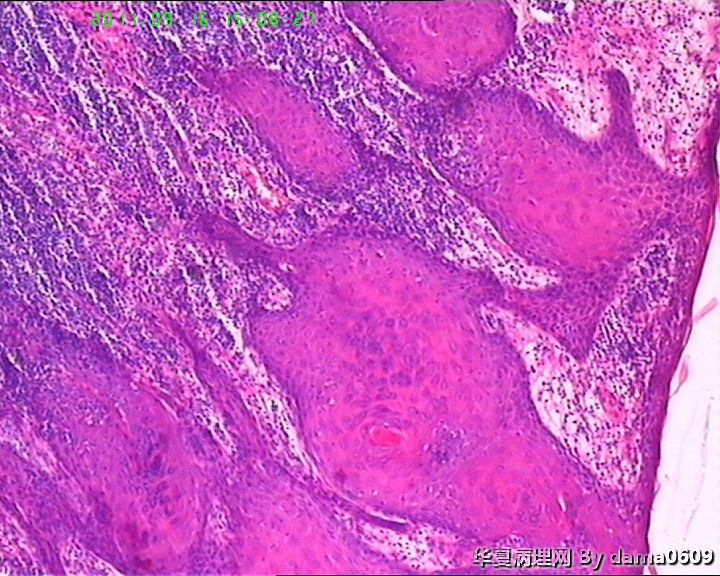

• 背部肿物,急请老师看看!!图4

图4

考虑高分化鳞癌伴慢性炎细胞浸润。

结合病史及镜下表现,如淋巴细胞浸润以皮下浅层为重、向下渐轻等,是否可符合书上的一个诊断:皮肤假性淋巴瘤(皮肤B细胞假性淋巴瘤)?学生自己没见过,还请老师多指教!!!谢!!